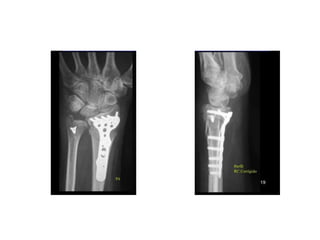

INCIDÊNCIAS PUNHO E MÃO